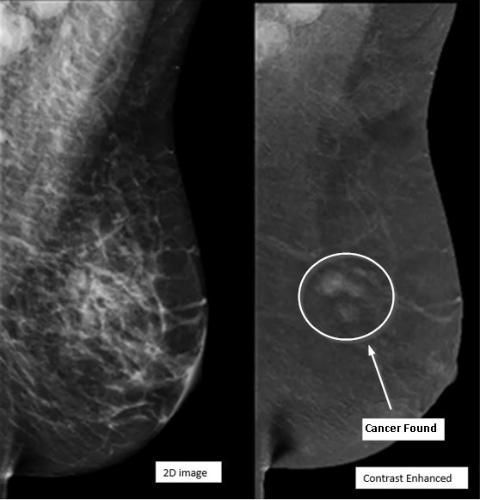

Contrast-Enhanced Mammography (CEM)

provides exceptional clarity to find breast

cancers that may not be visible in

traditional mammography. CEM may be

Contrast-Enhanced Mammography is

performed like a traditional mammogram

with the addition of intravenous contrast

- the same iodinated contrast that is used

for a CT exam. Using IV contrast helps

highlight areas of increased blood flow in

the breast, which can be a sign of cancer.